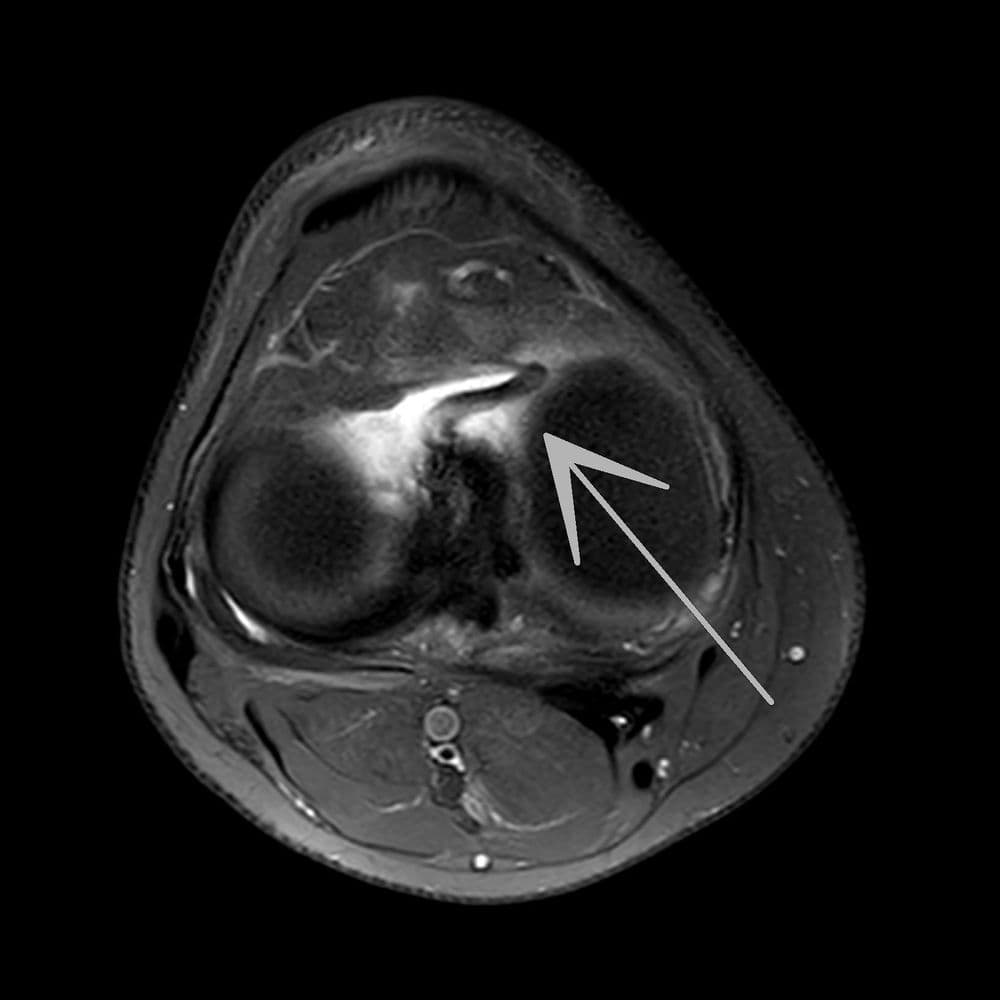

Traumatisme du genou au football sans contact

MRI